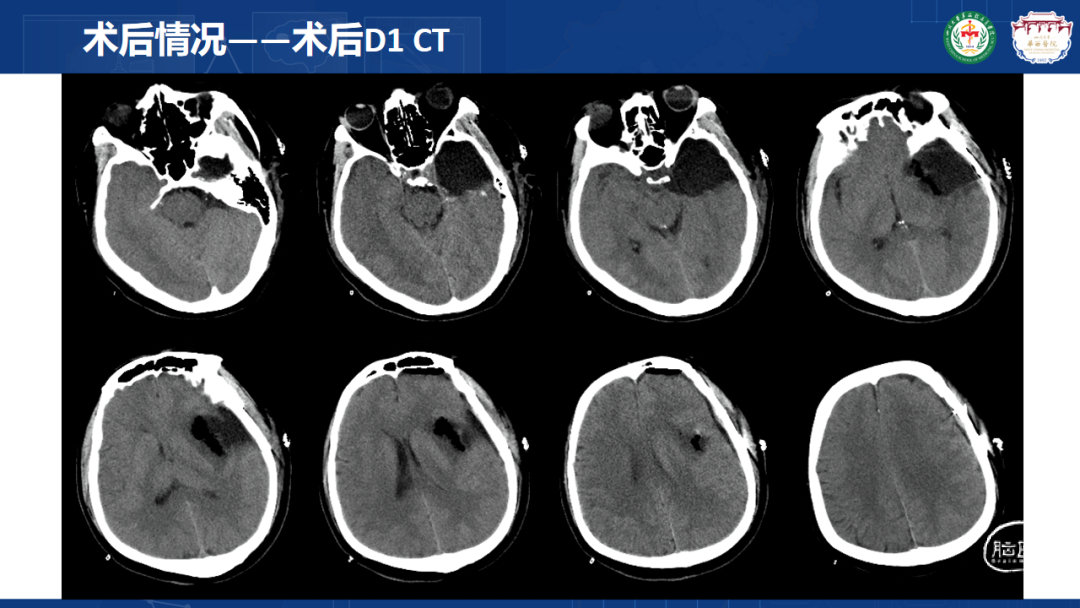

来自四川大学华西医院的曾云辉医师带来《岛叶胶质瘤手术及综合治疗》。该病例是一名41岁男性IT从业者,表现为头晕、右侧肢体麻木伴幻听,MRI显示左侧额颞岛叶占位累及海马头,DTl重建显示肿瘤包绕大脑中动脉分支。术中使用无牵拉技术联合多模态监测,经颞叶皮层造瘘切除病灶,术中重点保护侧裂静脉及M2段穿支血管。术后病理确诊为IDH突变型少突胶质细胞瘤(WHO 3级),规范实施同步放化疗联合6周期替莫唑胺辅助化疗。随访显示肿瘤控制良好,患者神经功能完整并恢复工作。